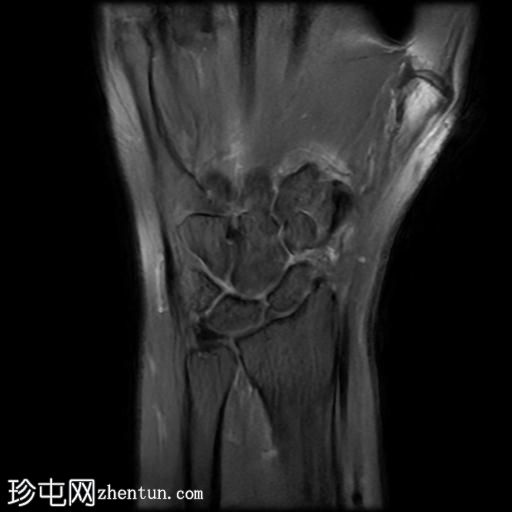

冠状位

T1加权像

桡侧腕屈肌腱鞘内可见液体信号,提示腱鞘炎

手部桡侧腕屈肌腱远端扁平,邻近的大多角骨嵴和舟骨结节可见反应性骨髓水肿

MRI结果提示存在桡侧腕屈肌腱病变,以及大多角骨和舟骨结节骨髓水肿。桡侧腕屈肌(FCR)肌腱病通常表现为腕关节掌侧(靠近桡侧)疼痛。这种情况通常是由于长期过度使用造成的,尤其是在肌腱与粗糙表面接触的部位。